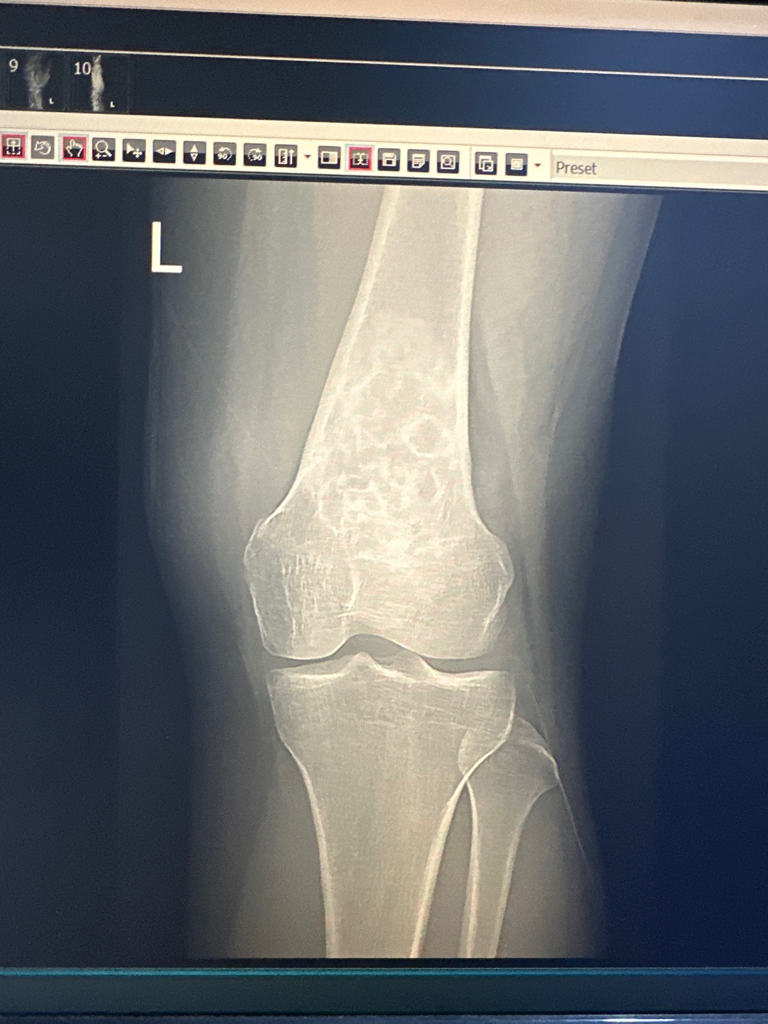

엑스레이 사진만으로는 평가가 제한됩니다. 이상 소견이 있는 것으로 보이는데 그것이 뼈 내부에 종양이 있는 것인지 아니면 다른 문제가 있는 것인지 등 구체적으로 감별이 어렵습니다. MRI 등 정밀 검사를 진행해보는 것이 필요해 보입니다.

지금 엑스레이만 봐서는 정확하게 알기 어렵지만 뼈에 종양이 발생하였을 가능성도 있습니다. 이를 정확하게 진단하기 위해서는 CT나 MRI를 촬영해 볼 필요가 있습니다.

안녕하세요. 영상의학과 전문의 최원제 의사입니다.

비골화성 섬유종 등 골종양의 소견이 의심됩니다.

MRI를 찍어보셔서 정확한 진단을 받아보시는 걸 추천드립니다.